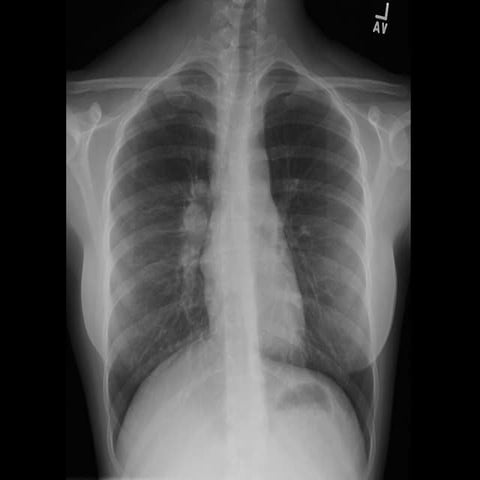

40 year old